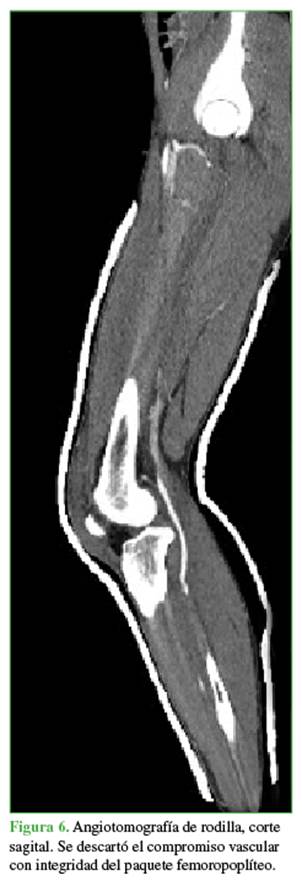

Las radiografías mostraban un aumento del espacio medial debido a la inestabilidad medial. Se ampliaron los estudios con una resonancia magnética (Figuras 4 y 5) para evaluar posibles tejidos o estructuras interpuestos y con una angiotomografía (Figura 6) para descartar una lesión vascular por el tiempo de evolución. Se observó un gran edema en los tejidos mediales, inclusive la cápsula y los tejidos mediales en la zona intercondílea, así como una persistente subluxación de la rodilla. Se descartó un compromiso vascular con integridad del paquete femoropoplíteo.